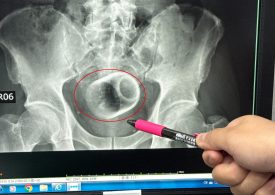

Teacup found in man’s bottom after he went to hospital complaining of constipation

A TEACUP was found in a man’s bottom after he went to hospital complaining of constipation. The patient had been unable to go to the…